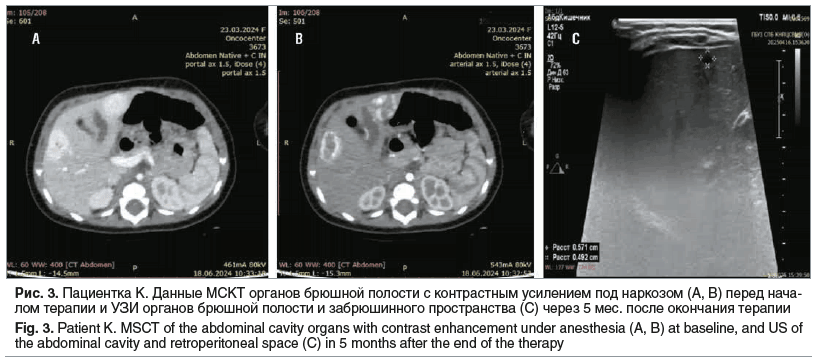

18.06.2024 выполнена мультиспиральная компьютерная томография (МСКТ) органов брюшной полости с контрастным усилением под наркозом: печень не увеличена, в паренхиме определяются гиподенсивные в нативной фазе (+44 HU) и гиперденсивные в артериальной и венозной фазах образования, контрастирующие от периферии к центру, выравнивающиеся по степени контрастирования в отсроченную фазу, размерами: в S3 14×8 мм (с601/91), в S4В 24×17 мм (с601/110), в S5 22×17 мм (с601/108) — гемангиомы (рис. 3).

Терапия пропранололом была завершена 15.11.2024 под дальнейшим контролем УЗИ (см. рис. 3). При УЗИ органов брюшной полости и забрюшинного пространства от 16.04.2025 (через 5 мес. после завершения курса лечения): в 4-м сегменте в 2 мм от капсулы печени определяется округлое, с неровными четкими контурами гипоэхогенное аваскулярное образование размерами 6×5 мм, дающее слабый эффект дорсального псевдоусиления сигнала. Заключение: УЗ-признаки кисты с плотными стенками правой доли печени (на месте бывшей гемангиомы). Пациентка в настоящее время находится под динамическим наблюдением детского онколога.